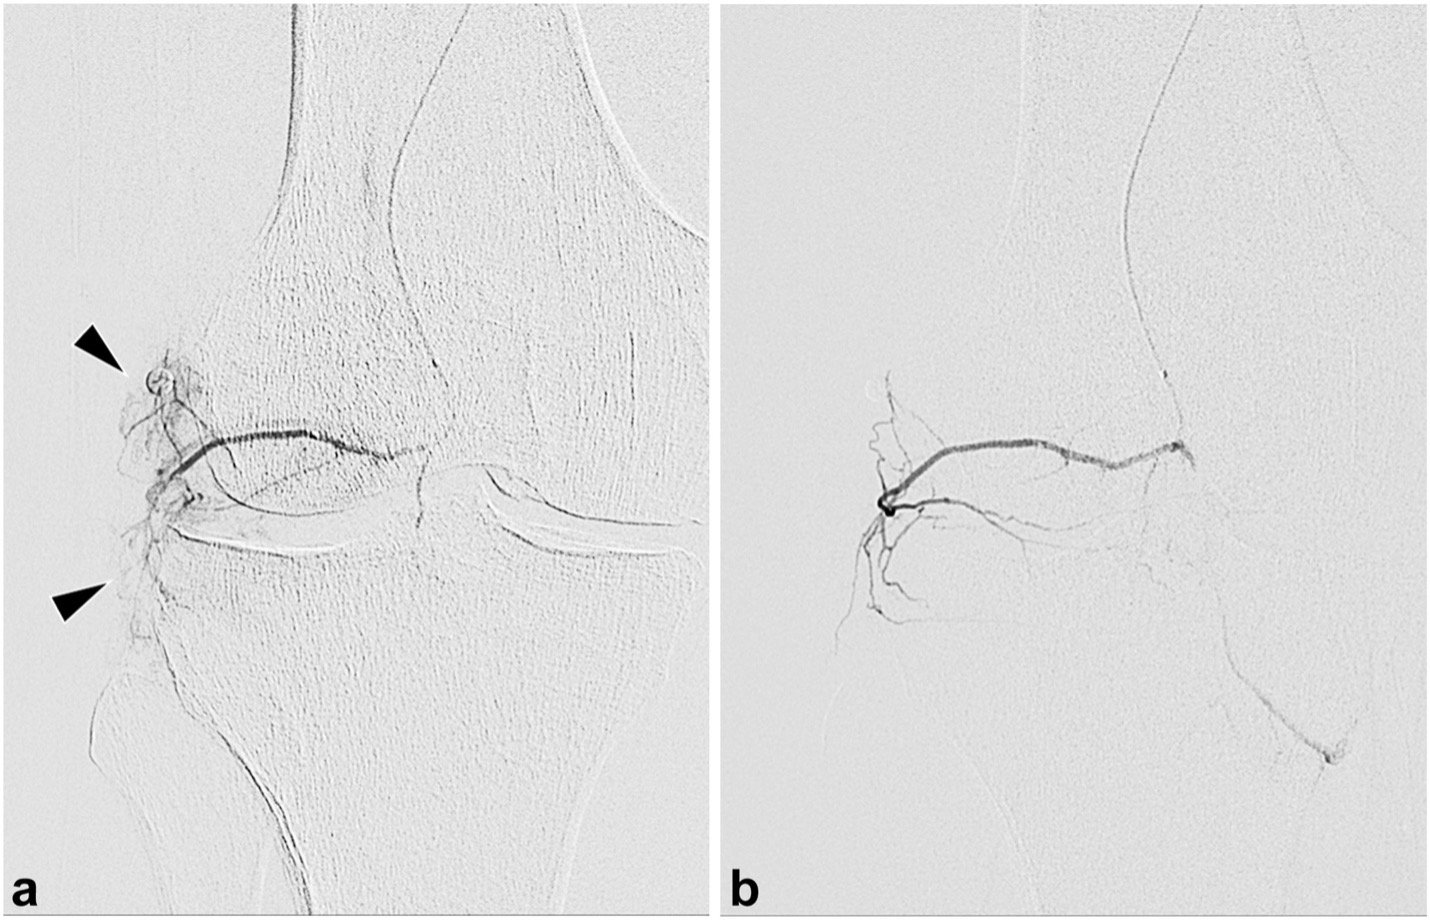

Cusumano, Lucas R. et al. Genicular Artery Embolization for Treatment of Symptomatic Knee Osteoarthritis: 2-Year Outcomes from a Prospective IDE Trial. JVIR. 2024;35(12):1768-1775

LC: GAE is gaining increasing acceptance as a treatment for knee osteoarthritis. However, the long-term data is limited specifically for this treatment. As a result, the focus of our study was to present the 2-year follow up data for our GAE patients. Our 1-year data was previously published by Siddharth A. Padia, MD, FSIR, in 2021 in the Journal of Bone and Joint Surgery. Two important features of our study that are worth noting is first, we used a relatively high bar for clinical success, which was at least a 50 percent decrease in Western Ontario and McMaster Universities Osteoarthritis Index (WOMAC) scores.

Second, we included patients with moderate to severe knee osteoarthritis judged on the Kellgren and Lawrence score that was two to four. We chose this because we thought it would more accurately represent the demographics seeking GAE treatments for pain relief for knee osteoarthritis.

LC: We found that the clinical outcomes after GAE were sustained for most patients at 2 years if they respond to initial treatment. Of the patients who responded at 12 months, 72% had durable response at 24 months and 28% had a relapse of symptoms. Of all the patients we treated, 47% demonstrated clinical success at 24 months and importantly, there were no long-term adverse events after GAE procedures.